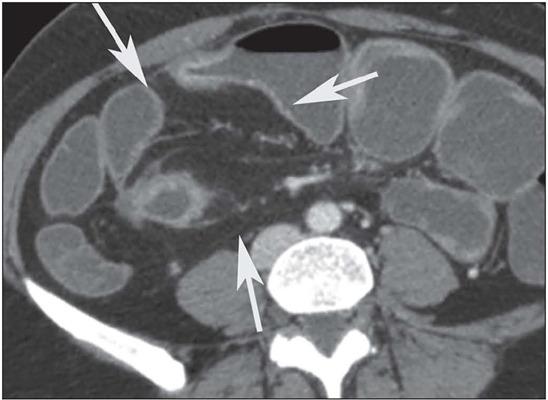

Crohn's disease is an inflammatory bowel disease that can affect any segment of the gastrointestinal tract. It has a variable clinical course, with alternating periods of disease activity and remission. Because the incidence and prevalence of Crohn's disease have been increasing, evaluation by imaging methods has become more important. The most widely used methods are computed tomography enterography, magnetic resonance enterography (as an elective examination), and contrast-enhanced computed tomography (in the context of emergency). Computed tomography enterography and magnetic resonance enterography are useful for diagnosis, follow-up, evaluation of complications, and prognosis. Both can be used in order to evaluate the small bowel loops and the associated mesenteric findings, as well as to evaluate other abdominal organs. They both also can detect signs of disease activity, fibrosis, penetrating disease, and complications. The interpretation of such changes is essential to the multidisciplinary approach, as is the standardization of the nomenclature employed in the reports. In this paper, we review and illustrate the imaging findings of Crohn's disease, using the standardized nomenclature proposed in the multidisciplinary consensus statement issued by the Society of Abdominal Radiology, the Society of Pediatric Radiology, and the American Gastroenterology Association, with recommendations for descriptions, interpretations, and impressions related to those findings.

克罗恩病是一种炎症性肠病,可累及胃肠道的任何节段。其临床病程多变,疾病活动期和缓解期交替出现。由于克罗恩病的发病率和患病率一直在上升,通过影像学方法进行评估变得更加重要。最常用的方法是计算机断层扫描小肠造影、磁共振小肠造影(作为选择性检查)和增强计算机断层扫描(在急诊情况下)。计算机断层扫描小肠造影和磁共振小肠造影对诊断、随访、并发症评估及预后判断均有帮助。两者均可用于评估小肠肠袢及相关肠系膜表现,以及评估其他腹部器官。它们还都能检测疾病活动、纤维化、穿透性病变及并发症的征象。对这些改变的解读对于多学科诊疗方法至关重要,报告中使用的命名标准化也同样重要。在本文中,我们使用腹部放射学会、儿科放射学会和美国胃肠病学会发布的多学科共识声明中提出的标准化命名,回顾并阐述克罗恩病的影像学表现,并对与这些表现相关的描述、解读及印象给出建议。